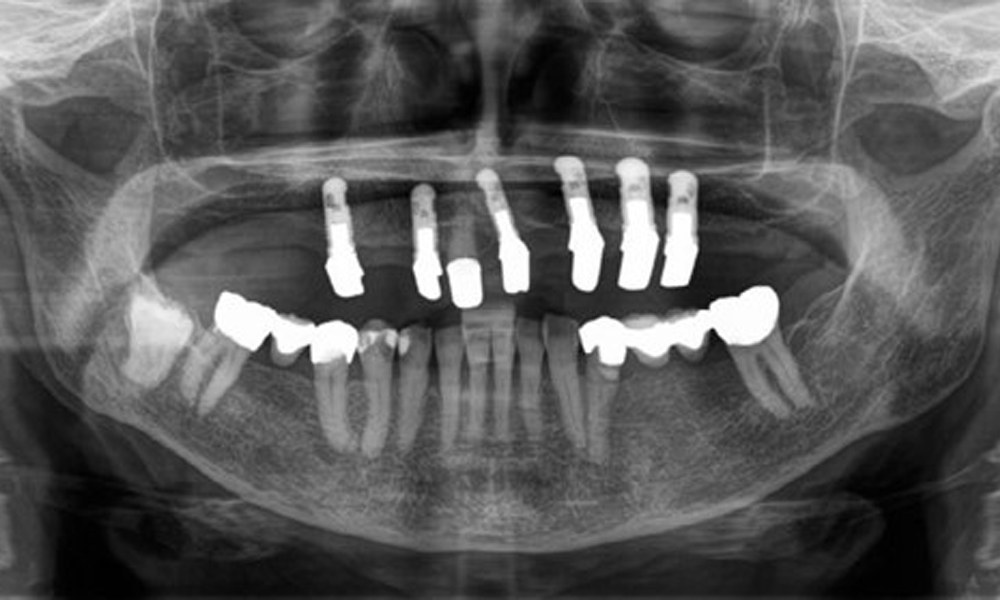

Die Patientin wurde vor über 25 Jahren mit einer kombinierten herausnehmbare Implantat-Teleskopprothese im Oberkiefer versorgt (Abb. 1, Abb. 2, Abb. 3) und ist sehr glücklich über ihren Zahnersatz. Im Unterkiefer hat die Patientin einen suffizienten festsitzenden Zahnersatz. (Abb. 4)

Der dentale Befund stellt sich wie folgt dar: Kombinierte herausnehmbare Implantat- und zahngetragene Teleskoparbeit auf Implantaten 15, 13, 21, 23, 24, 25 und Zahn 11 (Abb. 1, Abb. 2, Abb. 3). Im Unterkiefer ist die Patientin mit einem festsitzenden Zahnersatz versorgt. 37–34 sowie 45–47 haben suffiziente Brücken (Abb. 4). Kronenränder sind intakt, aktive kariöse Läsionen sind nicht vorhanden. An Zahn 43 zeigt sich eine Compositefüllung mit Randspalt. Im Unterkiefer liegen Rezessionen mit freiliegender Wurzeloberfläche zwischen 1 – 3 mm vor. Dies trifft auch für 11 zu.

Aus dem radiologischen Befund zeigt sich ein teilbezahntes Gebiss mit Implantaten im Oberkiefer an 15, 13, 21, 23, 24, 25 und einer Teleskopkrone 11. Im Unterkiefer sind suffiziente Brücken von 37–34 und 45–47 vorhanden. 48 ist retiniert. 43 distal besteht der Verdacht auf Sekundärkaries und 44 mesial Verdacht auf Sekundärkaries. 44 ist mit einer nicht röntgenopaken Unterfüllung versorgt.